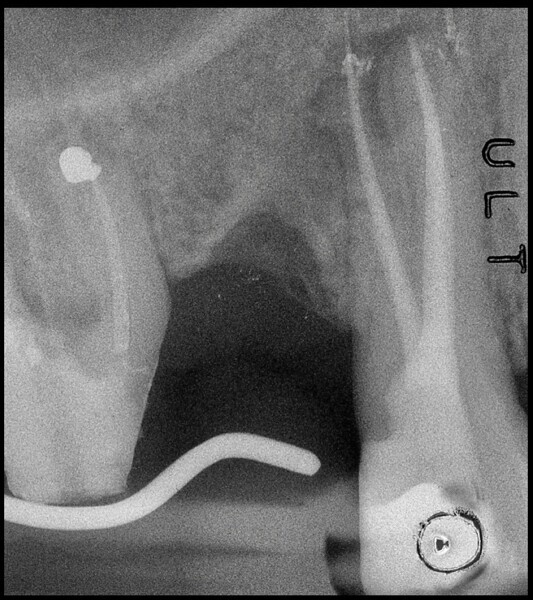

Use of 3D technology in the diagnosis and treatment of endodontic disease